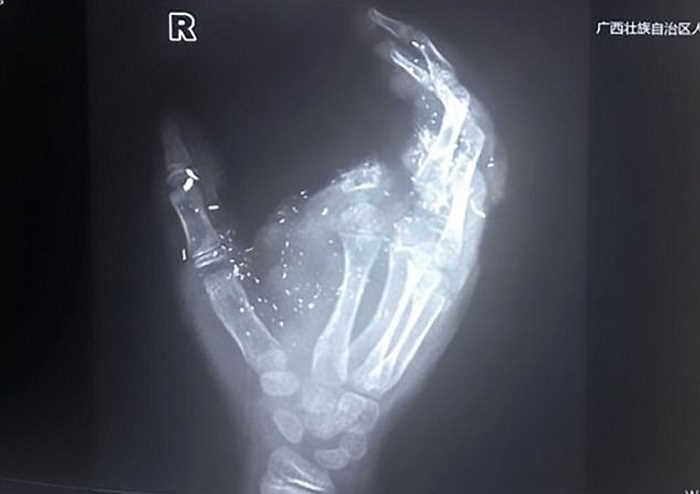

Түүний 12 настай хүү хуучин утсыг нь цэнэглэж байтал гэнэт дэлбэрч баруун гарын долоовор хуруу нь тасарч, өрөөсөн нүд нь сохорсон байна Эмч нар хүүд таван цаг мэс засал хийсний ачаар амьд үлдсэн ч хөгжлийн бэрхшээлтэй нэгэн болжээ. Хүүг гэмтээсэн утас Hua Tang VT-V59 гэх хятад утас байжээ.